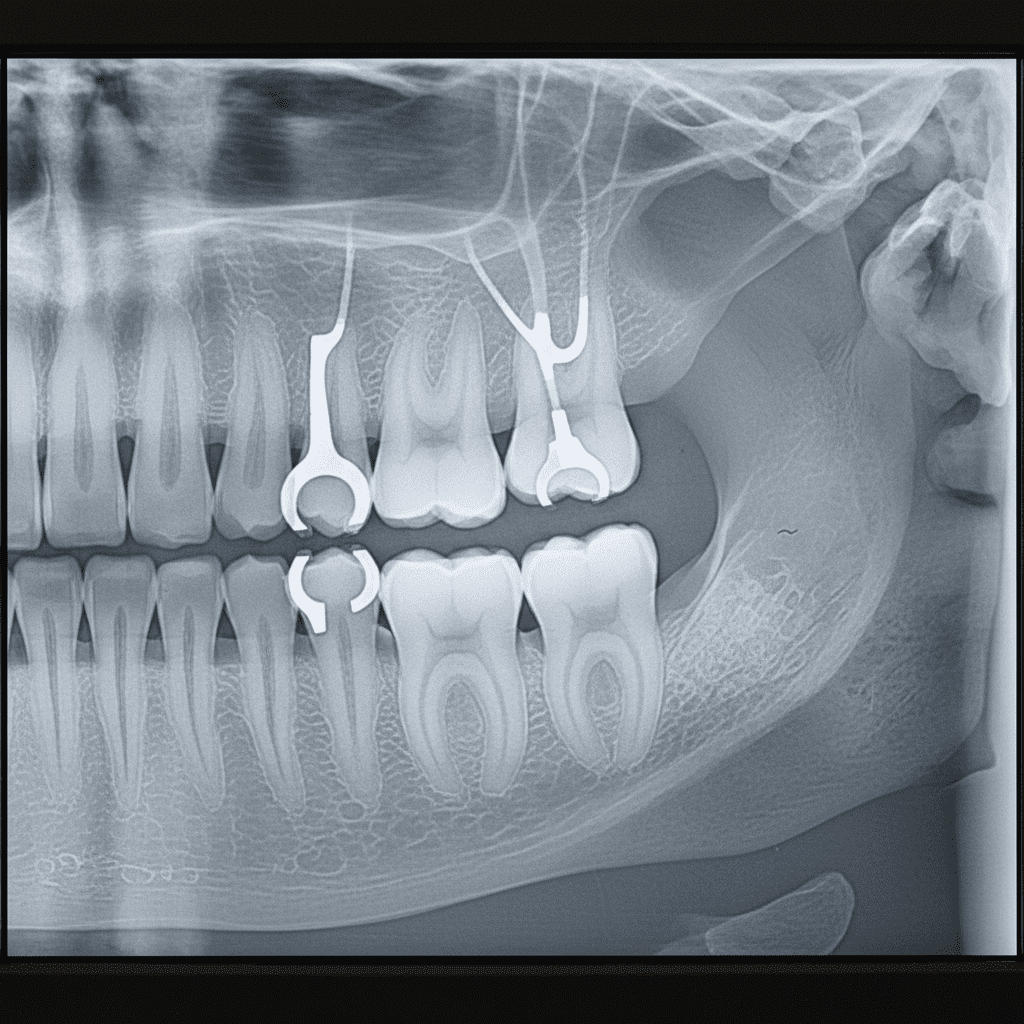

A presença de PPR em uma radiografia pode modificar substancialmente a imagem. As próteses podem ser identificadas como artefatos radiográficos, o que pode dificultar a interpretação das estruturas subjacentes. Os materiais utilizados na confecção das PPR, como alumínio e outros metais, costumam apresentar opacidades diferentes nas radiografias, o que pode mascarar detalhes importantes do osso alveolar e dos dentes adjacentes.

Identificação de Artefatos Radiográficos

Os artefatos radiográficos são distorções que aparecem nas imagens devido a diversos factores, como os materiais das próteses. Quando um paciente está usando PPR, essas distorções podem, muitas vezes, criar ilusões que dificultam a avaliação clínica. A habilidade do radiologista em distinguir entre o que é um artefato e a estrutura que está sendo examinada é crucial para um diagnóstico preciso.